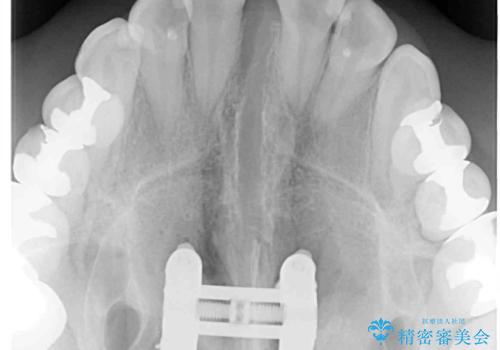

上顎骨の幅が下顎骨よりも小さいので、拡大装置により骨幅を広げて上下関係を改善し、その後インビザラインにて歯並びを整えることとしました。